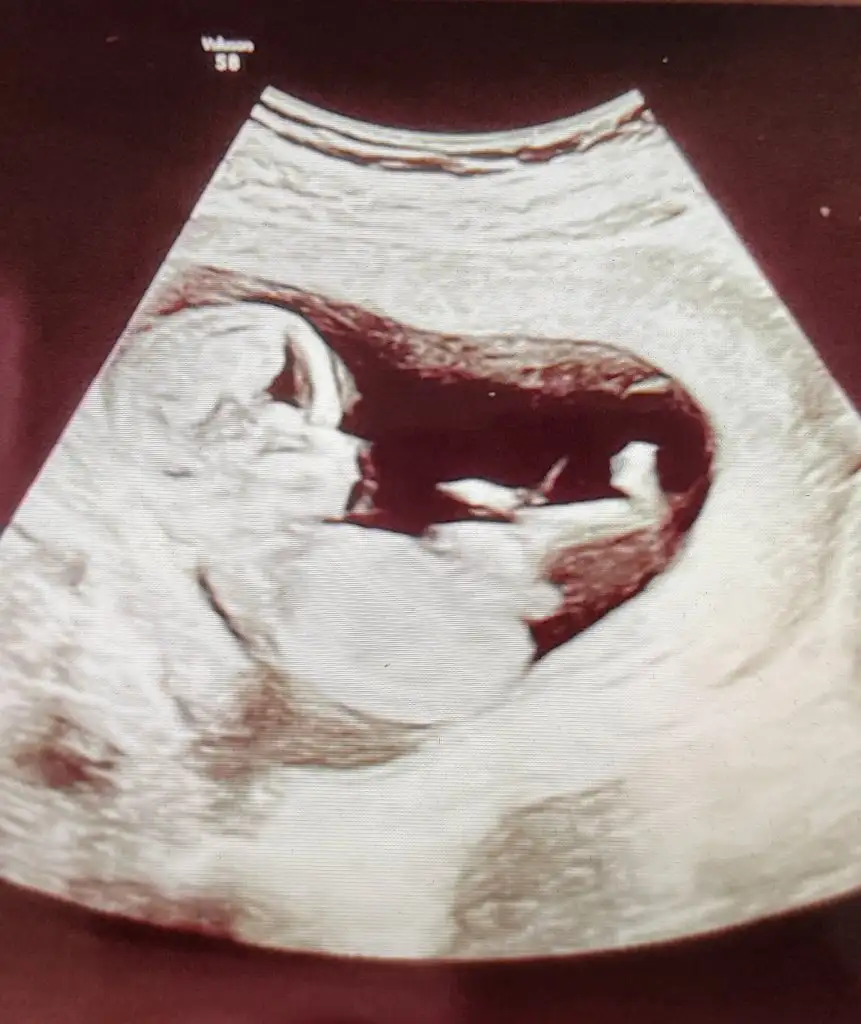

dr soylemeden siz gorun genital nub teorisi ( bebegin cinsiyeti)

Bu bebeğe de bakarmisiniz 14 haftalık